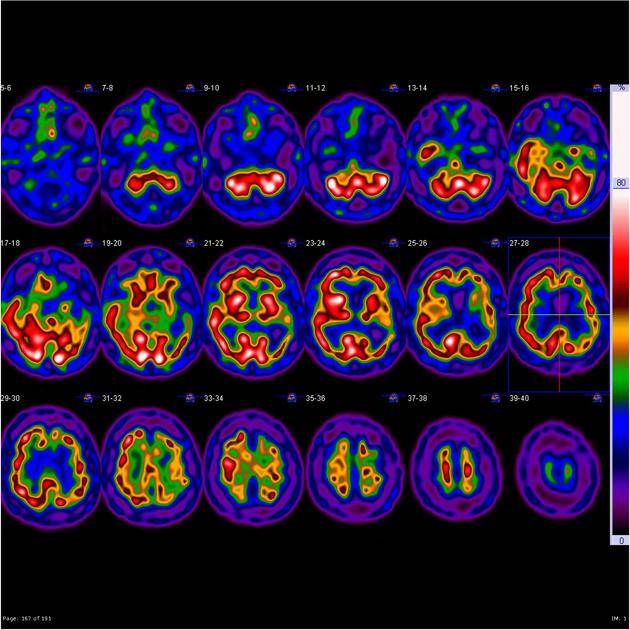

Professor Jason Warren and Dr Jon Rohrer at UCL have been developing a large programme of work to better understand frontotemporal dementia. This includes a project run by Professor Warren and funded by Alzheimer’s Society that uses brain scans to better identify frontotemporal dementia. These scans can tell us a lot about a person’s brain health, including whether their brain is shrinking or if there are any signs of damage.

Professor Warren and his team can link changes seen on brain scans with other symptoms of the condition to understand what is happening in people who are affected. This in turn will help diagnosis and early detection of frontotemporal dementia, allowing people to be enrolled in trials sooner.